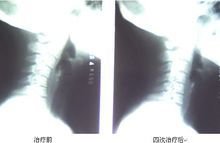

关于颈椎曲度变直,反弓的治疗,我发一张治疗前后的对比片子大家看看,以后会陆续的发一些新看起来也正常了